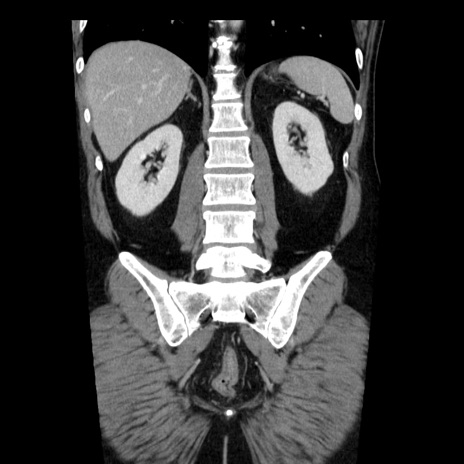

症例29(冠状断像)

【症例】40歳代男性

【現病歴】2日前から胃痛あり。徐々に周期的な激痛に変化した。本日になっても激痛があるため受診。

【身体所見】意識清明、BT 38-39℃台あり、腹部:膨満、やや硬、右下腹部に圧痛あり。

【データ】WBC 8500、CRP 23.26